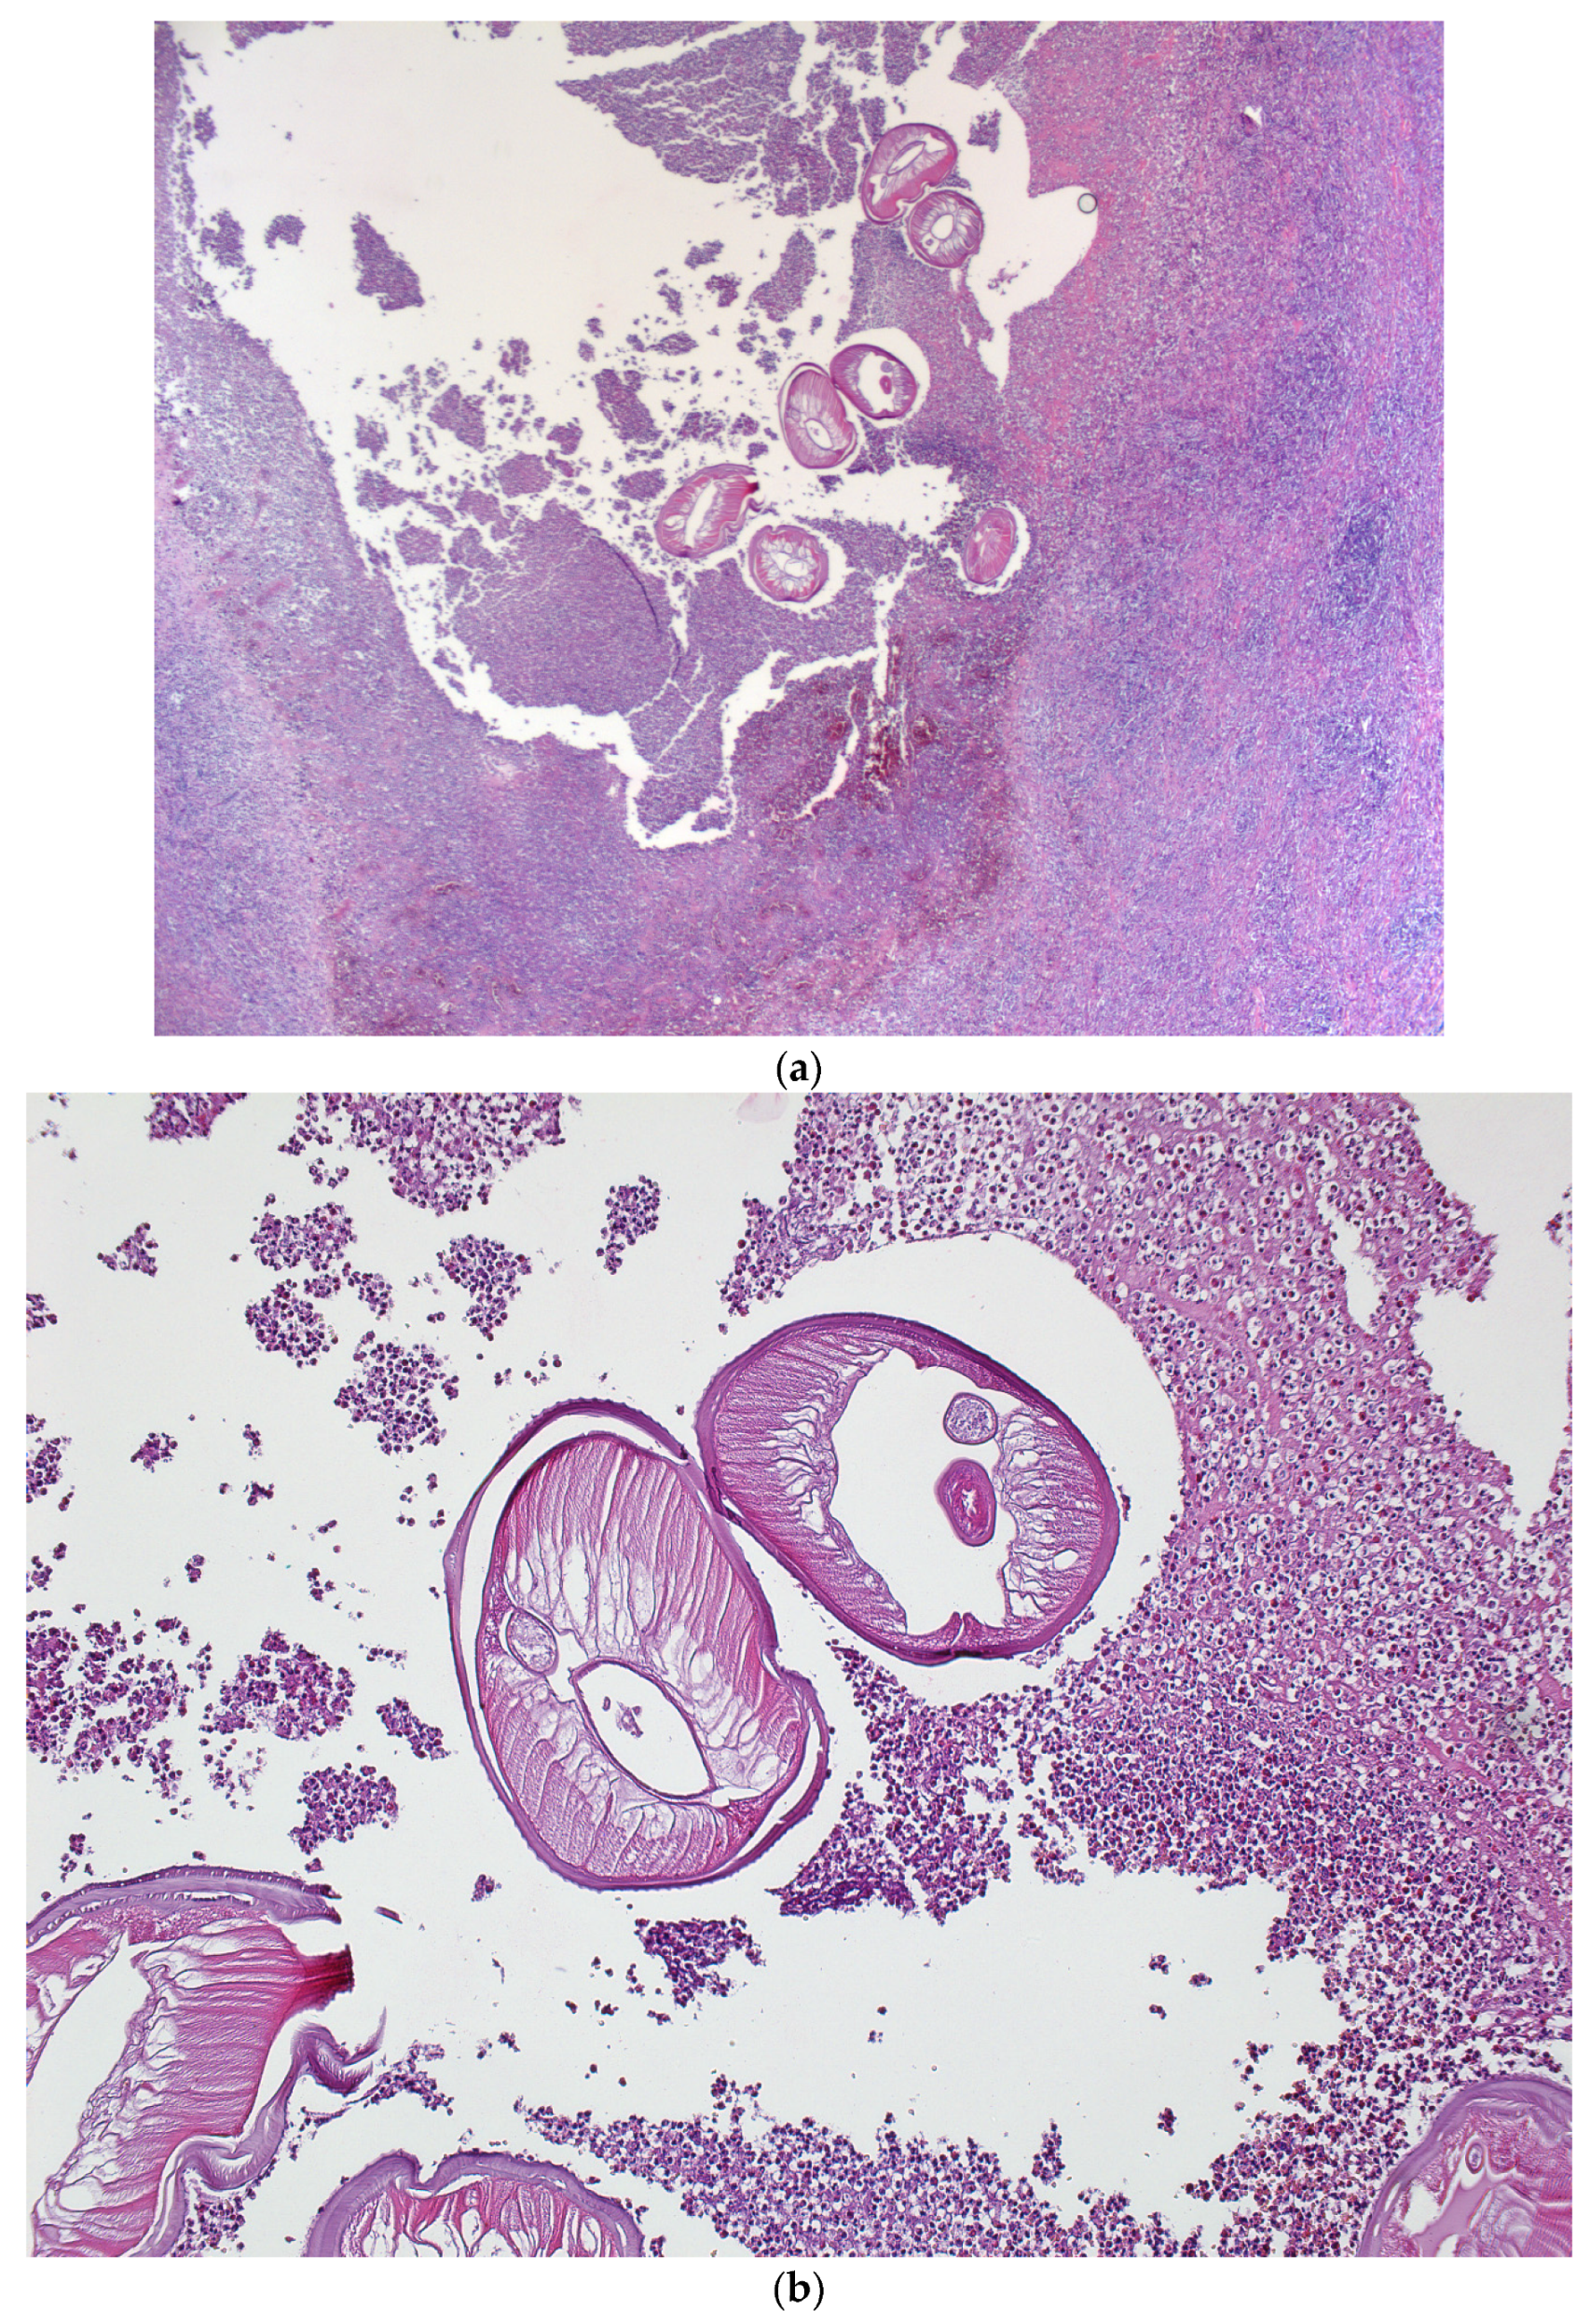

A Rare Case of Dirofilariasis in the Genian Region

2. Case Report